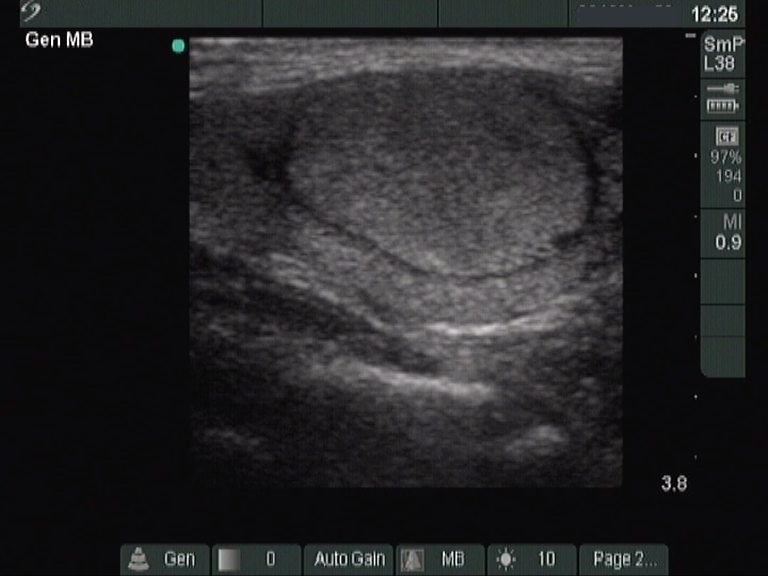

The composition of the nodule - case 1457 (ultrasonographic picture 6)

Left lobe, longitudinal scan.